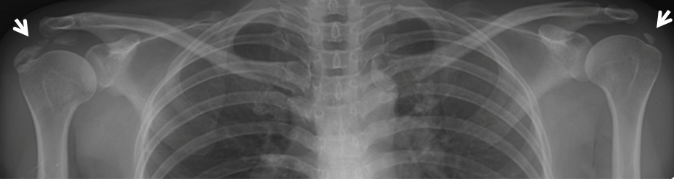

석회화건염이란?

석회화건염은 어깨에 연결된 인대에 석회(돌)가 침착되어 통증을 유발하는 질환으로, 칼슘이 침착되어 결정이 만들어져 극심한 통증을 호소하게 됩니다. 환자의 상태에 따라 석회가 생겼다가 저절로 없어지기도 하지만, 극심한 통증으로 응급실을 찾는 경우도 많습니다.

석회화건염 이미지